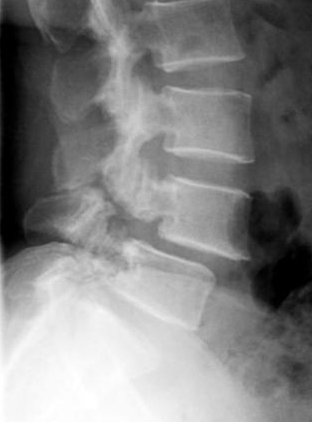

예를 들어서 서있는 경우에 장요근이 단축이 되어 있는경우장요근의 구조로 인해서 허리를 과도하게 앞으로꺾이는 모습으로 만들어 버립니다~이런모습을 요추전만(Lordosis)이라고 합니다.

과한 요추전만(Lordosis)은 보기에 좋을 수도 있겠지만허리 후면에 과한 압력을 줄 수 있습니다.

처음에는 허리에 가벼운 통증으로 시작 될 수 있지만척추 후관절의 지속적인 압박은 후관절이 부서지는척추분리증(spondylolysis)에서, 더 나아가면후관절의 지지력을 상실해서 척추가 앞으로미끄러지는 현상이 나타나는데이것이 바로 척추전방전위증(spondylolisthesis)입니다.